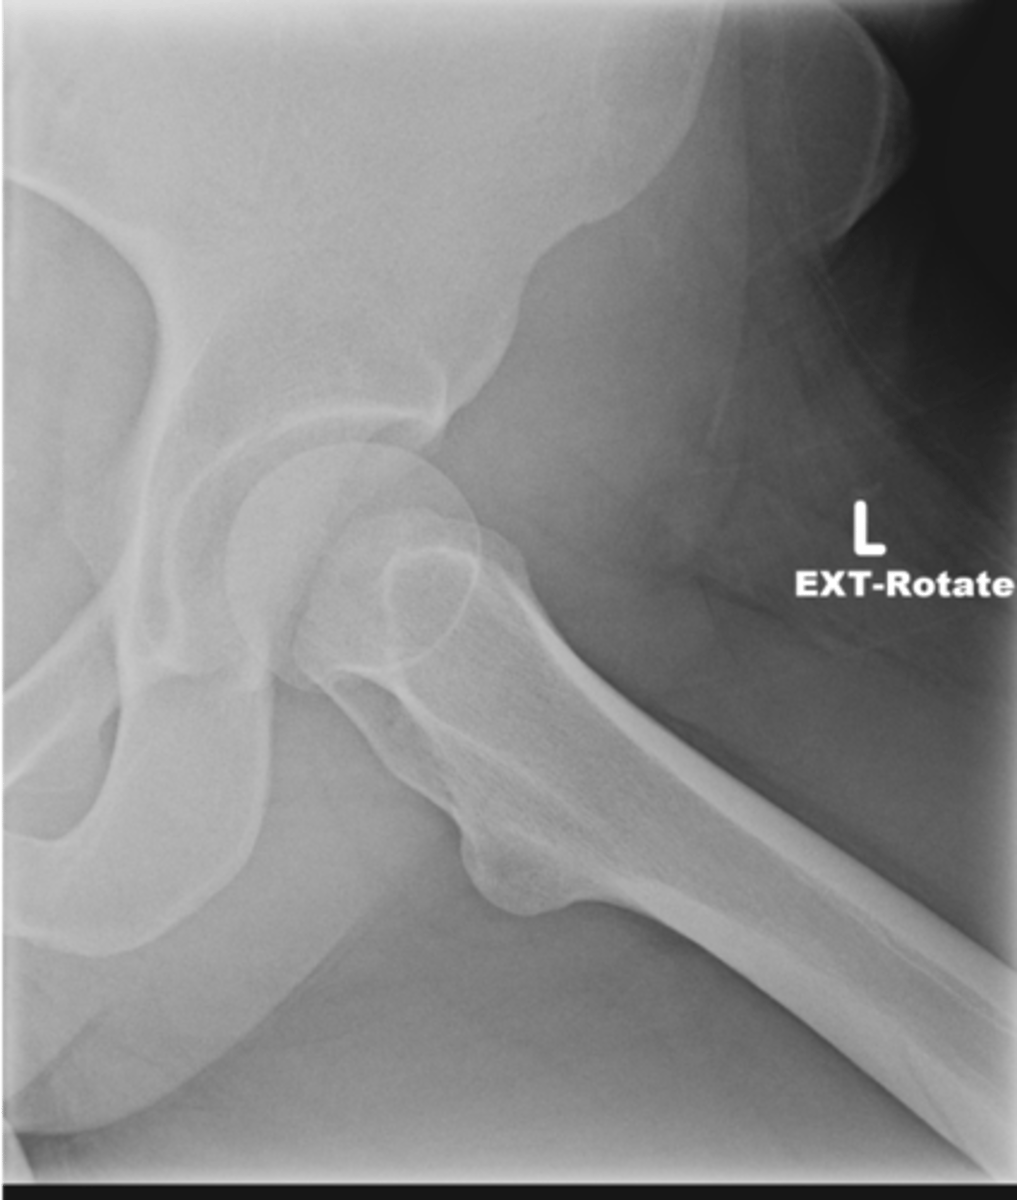

28

Left AP hip

View?

<p>View?</p>